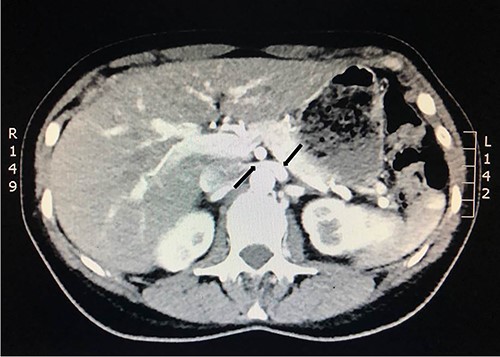

To investigate the bleeding source, she subsequently had a CT renal angiogram 3 days later that showed a narrow angle between origin of SMA and the aorta (Fig. 3) with multifocal areas of hypoattenuation throughout the left renal cortex (Fig. 4). It showed a compression ratio of 3.25 (diameter of pre-compressed vein =6.5 mm; diameter of compressed vein =2 mm) (Fig. 5).

Computed tomography angiogram on presentation showing pre-compressed LRV (right arrow); and compressed LRV (left arrow).